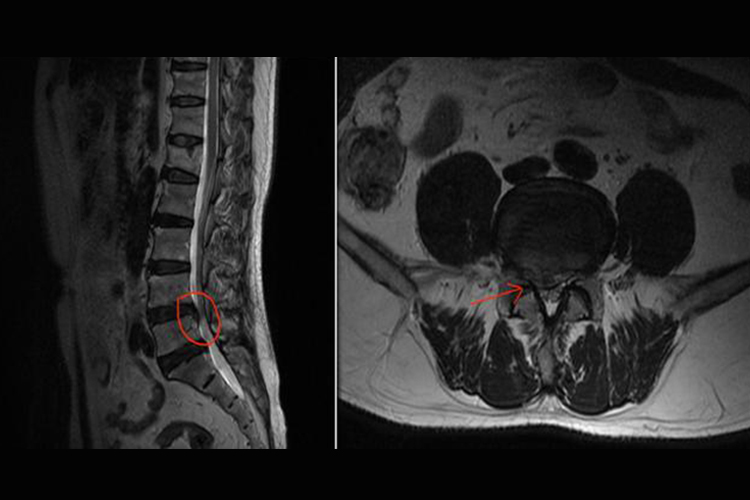

腰椎间盘突出症压迫神经表现为椎间盘组织在椎管内前方压迫硬膜囊,使硬膜囊向一侧推移,或前外侧压迫神经根,使神经根向侧后方向移位。